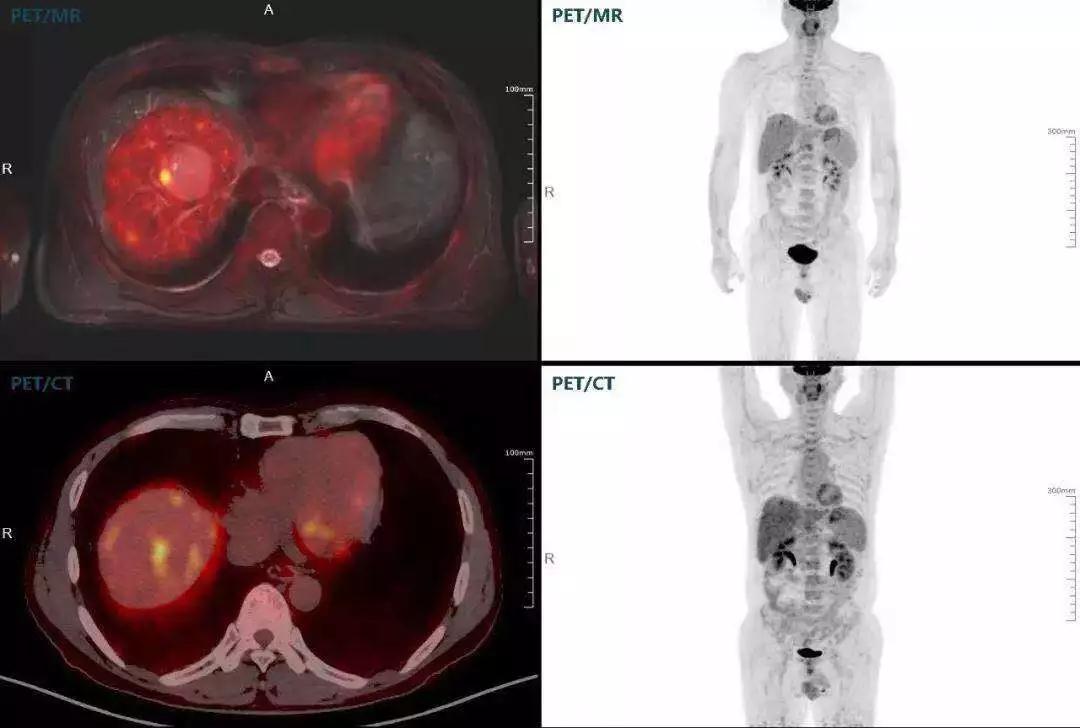

肝癌

聯(lián)影“時空一體”超清TOF PET/MR搭載的壓縮感知技術,能夠同時實現(xiàn)16期成像,精準捕獲肝臟動態(tài)影像的每一瞬間,同時兼顧早期與晚期等全部期相的完整病灶信息,實時、全方位鎖定病灶。同時,基于其2.8mm超高分辨率,能夠精細呈現(xiàn)腫瘤邊界信息,捕捉局部微小病灶與遠端轉移灶,助力醫(yī)生精準診斷。

(對于同一例肝臟惡性腫瘤,PET-CT與PET/MR成像對比??梢钥吹?,聯(lián)影PET/MR圖像對腫瘤邊界和FDG高濃聚區(qū)域清晰顯示。)